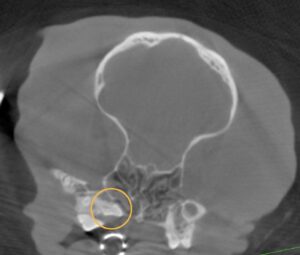

全身麻酔下で頭部CT、歯科レントゲン検査を実施しました。

その結果、上顎の奥歯が、顎の骨の中に完全に横向きに埋伏していることが分かりました。

埋伏歯とは、本来生えてくるはずの歯が、骨の中に埋まったままになっている状態です。

外からは見えないため、視診や歯磨きでは気づくことができません。